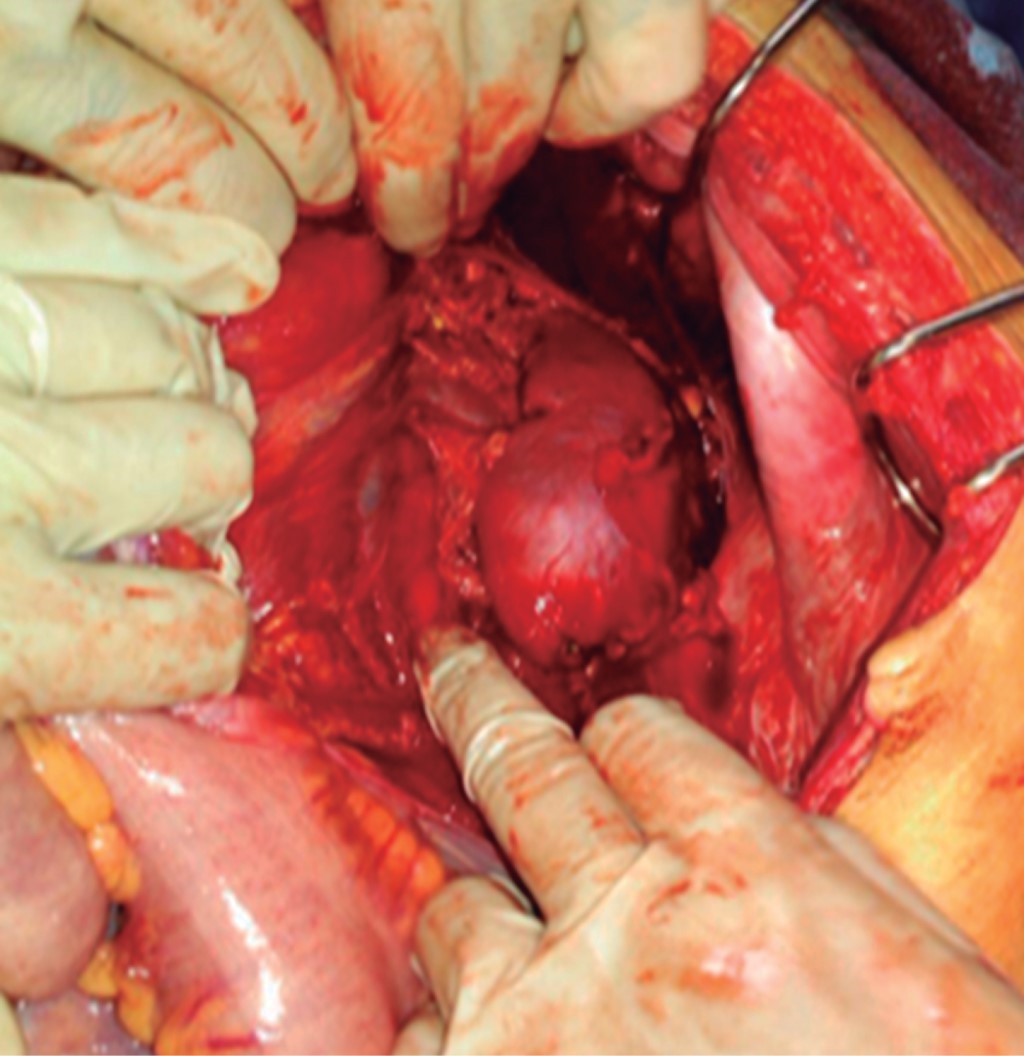

Piel: morena, se evidencia palidez cutánea mucosa generalizada, llenado capilar menor de tres segundos. Cardiopulmonar: tórax simétrico, hipoexpansible a predominio de hemitórax derecho, se evidencian múltiples orificios por proyectil de arma de fuego en región inferior de hemitórax posterior izquierdo y tercio inferior de hemitórax posterolateral derecho, ruidos respiratorios disminuidos en tercio inferior hemitórax derecho sin agregados. Ruidos cardiacos rítmicos y regulares sin soplo ni galope. Abdomen: distendido, ruidos hidroaéreos disminuidos, doloroso a la palpación con signos de irritación peritoneal generalizada. Región lumbar: se evidencian orificios por proyectil de arma de fuego tipo descargas múltiples en región lumbar bilateral a predominio derecho (Figura 1). Tacto rectal: esfínter anal externo tónico, heces en ampolla, fondo de saco abombado. Extremidades: simétricas, eutróficas sin edema. Neurológico: consciente orientada en tiempo, espacio, persona.

Es llevada a quirófano, se realiza laparotomía exploradora observando como hallazgos: 1. 1,500 cm3 de hemoperitoneo + 1,000 cm3 de sangrado transoperatorio. 2. Hematoma retroperitoneal en zona II derecha en expansión. Hematoma en zona II retroperitoneal izquierda no expansivo. 3. Múltiples lesiones < 0.5 cm a nivel renal derecho con compromiso del hilio. 4. Múltiples lesiones < 0.5 cm a nivel renal izquierdo no sangrante sin compromiso del hilio (Figura 2). 5. Dos lesiones de 0.5 cm de fondo vesicular. 6. Múltiples lesiones < 50% de colon ascendente hasta ángulo hepático de colon transverso. 7. Múltiples lesiones de asa delgada < 50% de 175 cm hasta 250 cm de asa fija (a 40 cm de válvula ileocecal). 8. Lesión < 50% de colon descendente. 9. Múltiples lesiones hepáticas puntiformes < 1 cm de profundidad no sangrante en segmento V, VI, VII y VIII. 10. Lesión puntiforme de serosa en cara posterior en cuerpo de estómago. 11. Lesión de hemidiafragma derecho de 2 cm hacia su inserción posterior. 12. Lesión de 1 cm de profundidad y 1 cm de longitud en polo inferior de bazo no sangrante. 13. Lesión < 0.5 cm de ovario derecho no sangrante y 14. Resto de órganos indemnes.

Figura 2